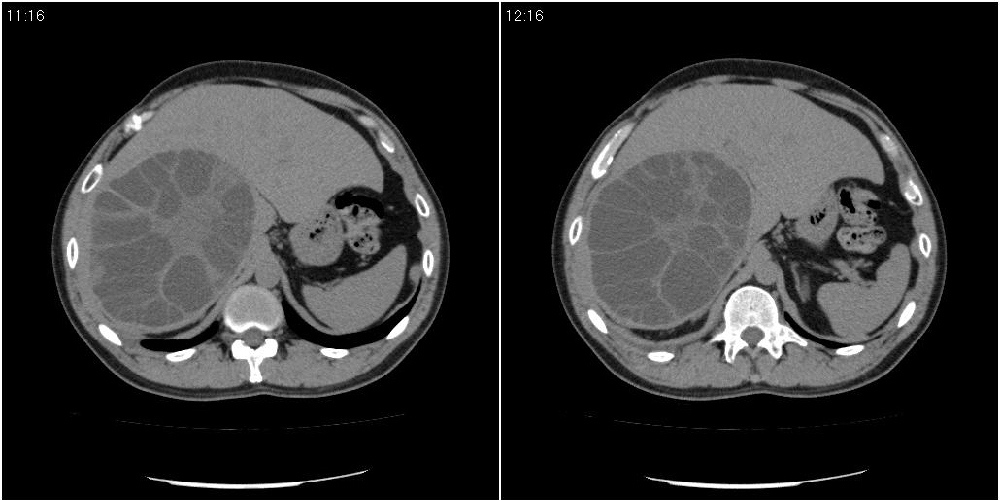

该患者70岁男性,手术后10年,现复查。2008年6月份本人曾经发过一极其类似的病例,只是部位略有差异。

肝脏多房性包虫囊肿

水上浮莲征,肝包虫囊肿。

肝脏及右侧胸腔包虫病。

大囊套小囊!肝脏多房性包虫囊肿